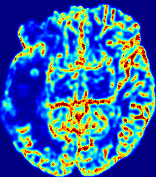

Slice #1Slice #2Slice #3Slice #4Slice #5Slice #6Dgtsuperscript𝐷gtD^{\text{gt}}Refer to captionRefer to captionRefer to captionRefer to captionRefer to captionRefer to caption(a)Refer to captionRefer to captionRefer to captionRefer to captionRefer to captionRefer to caption(b)Refer to captionRefer to captionRefer to captionRefer to captionRefer to captionRefer to caption(c)Refer to captionRefer to captionRefer to captionRefer to captionRefer to captionRefer to caption(d)Refer to captionRefer to captionRefer to captionRefer to captionRefer to captionRefer to caption(e)Refer to captionRefer to captionRefer to captionRefer to captionRefer to captionRefer to caption(f)Refer to captionRefer to captionRefer to captionRefer to captionRefer to captionRefer to captionRefer to caption000.060.060.060.120.120.120.180.180.180.240.240.240.300.300.30(mm2/s)𝑚superscript𝑚2𝑠(mm^{2}/s)

Figure 13: PIANO effectiveness and robustness testing: diffusion imaging via diffusion. Top row shows Dgtsuperscript𝐷gtD^{\text{gt}} used for simulating the ground truth pure diffusion. (a)-(f) refer to the results for D𝐷D estimated from the ground truth pure diffusion image time-series where Rician noise at levels 0%, 2%, 4%, 6%, 8%, 10% was added respectively.

Similarly, starting from the same initial condition C0superscript𝐶0C^{0} as in the ‘Advection Imaging’ experiment for each patient, we simulate concentration time-series {Cti(Ω)|i=0, 1,, 40}conditional-setsuperscript𝐶subscript𝑡𝑖Ω𝑖0140\{C^{t_{i}}\in\mathbb{R}(\Omega)|i=0,\,1,\,\ldots,\,40\} via a diffusion PDE, where we define the ground truth diffusivity D:=Dgtassign𝐷superscript𝐷gtD:=D^{\text{gt}} via the ADC map of the ISLES 2017 training set (ADC values are scaled by 0.000010.000010.00001 to ensure numerical stability):

Note this is likely not a spatially representative ground-truth for perfusion imaging, as it measures different effects from diffusion imaging. However, we still use it as a quasi-realistic pattern of diffusivity in the brain. We also added 2%, 4%, 6%, 8%, 10% levels of Rician noise to obtain simulations of ‘Diffusion Imaging’. The estimated Destsuperscript𝐷estD^{\text{est}} given concentrations of all noise levels for one patient are shown in Fig. 13, PIANO estimation results for all patients are summarized in Fig. 11 (b). Again, PIANO demonstrates its capability to recover the underlying diffusion field. In Fig. 13, when the noise level is increasing, some noisy patterns indeed appear in the associated Destsuperscript𝐷estD^{\text{est}}. Note that the ground truth diffusivity applied in this simulation experiment is about ten times larger than the diffusivity estimated in reality (Fig. 3, Fig. 4).